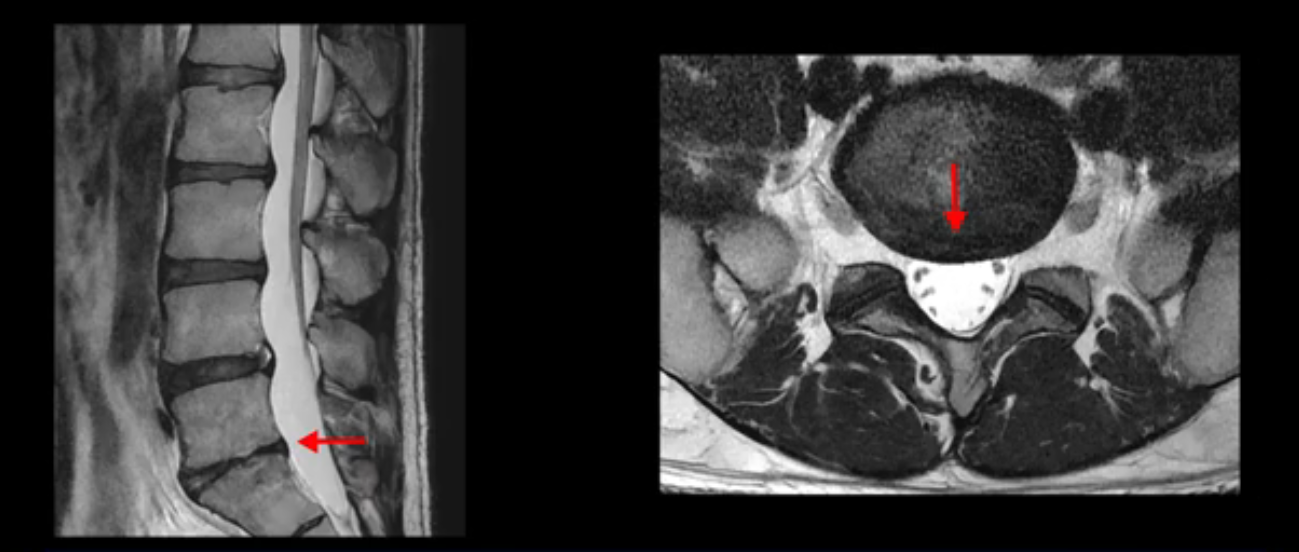

우선 이분 MRI를 보면 허리 모든 마디의 디스크가 퇴행되어 있고

여러 마디의 디스크가 조금씩 밀려나와 보이고, 디스크 섬유륜도 찢어져 보이는 마디도 보입니다.

그런데 이분의 증상과 MRI가 전혀 일치하지 않는데, 왜 그런지 지금부터 자세히 설명드립니다. 이분 증상은 앉으면 엉치와 허리가 심하게 아파 10분 이상 앉는 게 어렵고 양쪽 발가락이 앉아있을 때나 누워있을 때 다 저립니다. 걸을 때도 아파서 10분 걷기도 어렵습니다. MRI를 마디마디 살펴보면 1번 2번은 오른쪽으로 살짝 밀려나온 디스크가 있지만 전혀 심하지 않고, 뒤에 또 설명하겠지만 최근에 밀려나온 급성 디스크가 아니고 오래된 디스크로 판단됩니다.

4번 5번은 가운데로 섬유륜이 찢어져서 디스크가 살짝 밀려나와 있지만 역시나 최근에 찢어지고 밀려나온 걸로 판단되지 않고 오래 전에 찢어진 흔적으로 보입니다.

5번 1번 역시 가운데로 디스크 조금 밀려 나와있지만 신경 공간 넓이는 아주 넓어서 신경 눌림 있을 거라고 예상이 안됩니다.

이분은 어떤 한 병원에서 디스크 내장증 얘기를 들으셨는데요. 여기 보시는 것처럼 4번 5번의 하얀 HIZ(High Intensity Zone)을 보고 디스크 내장증의 근거로 얘기하는 병원들이 있는데,

이 HIZ는 섬유륜이 찢어졌다가 이미 아문 뒤에도 얼마든지 보일 수 있는 흔적일 가능성이 있어서 재채기를 하면 아픈지, 허리를 구부릴 때 날카로운 통증이 생기는가 등의 증상으로 구별해야 하는데 MRI만 보고 HIZ가 보이면 그게 마치 통증의 원인인 것처럼 얘기하는 의사들이 있습니다. 이분 MRI를 자세히 보고 증상을 정말 자세히 들어본 의사가 있었더라면 다른 환자분들처럼 증상과 MRI가 일치하지 않는다는 얘기를 들을 수 있었을 텐데 이분은 그런 얘기는 듣지 못했습니다.